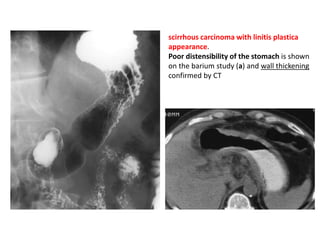

– Stenotic phase – scarring and fibrosis narrowing the gastric

antrum and pylorus into a funnel or “rams-horn”shape.

– D/D – other granulomatous diseases, scirrhous gastric

carcinoma